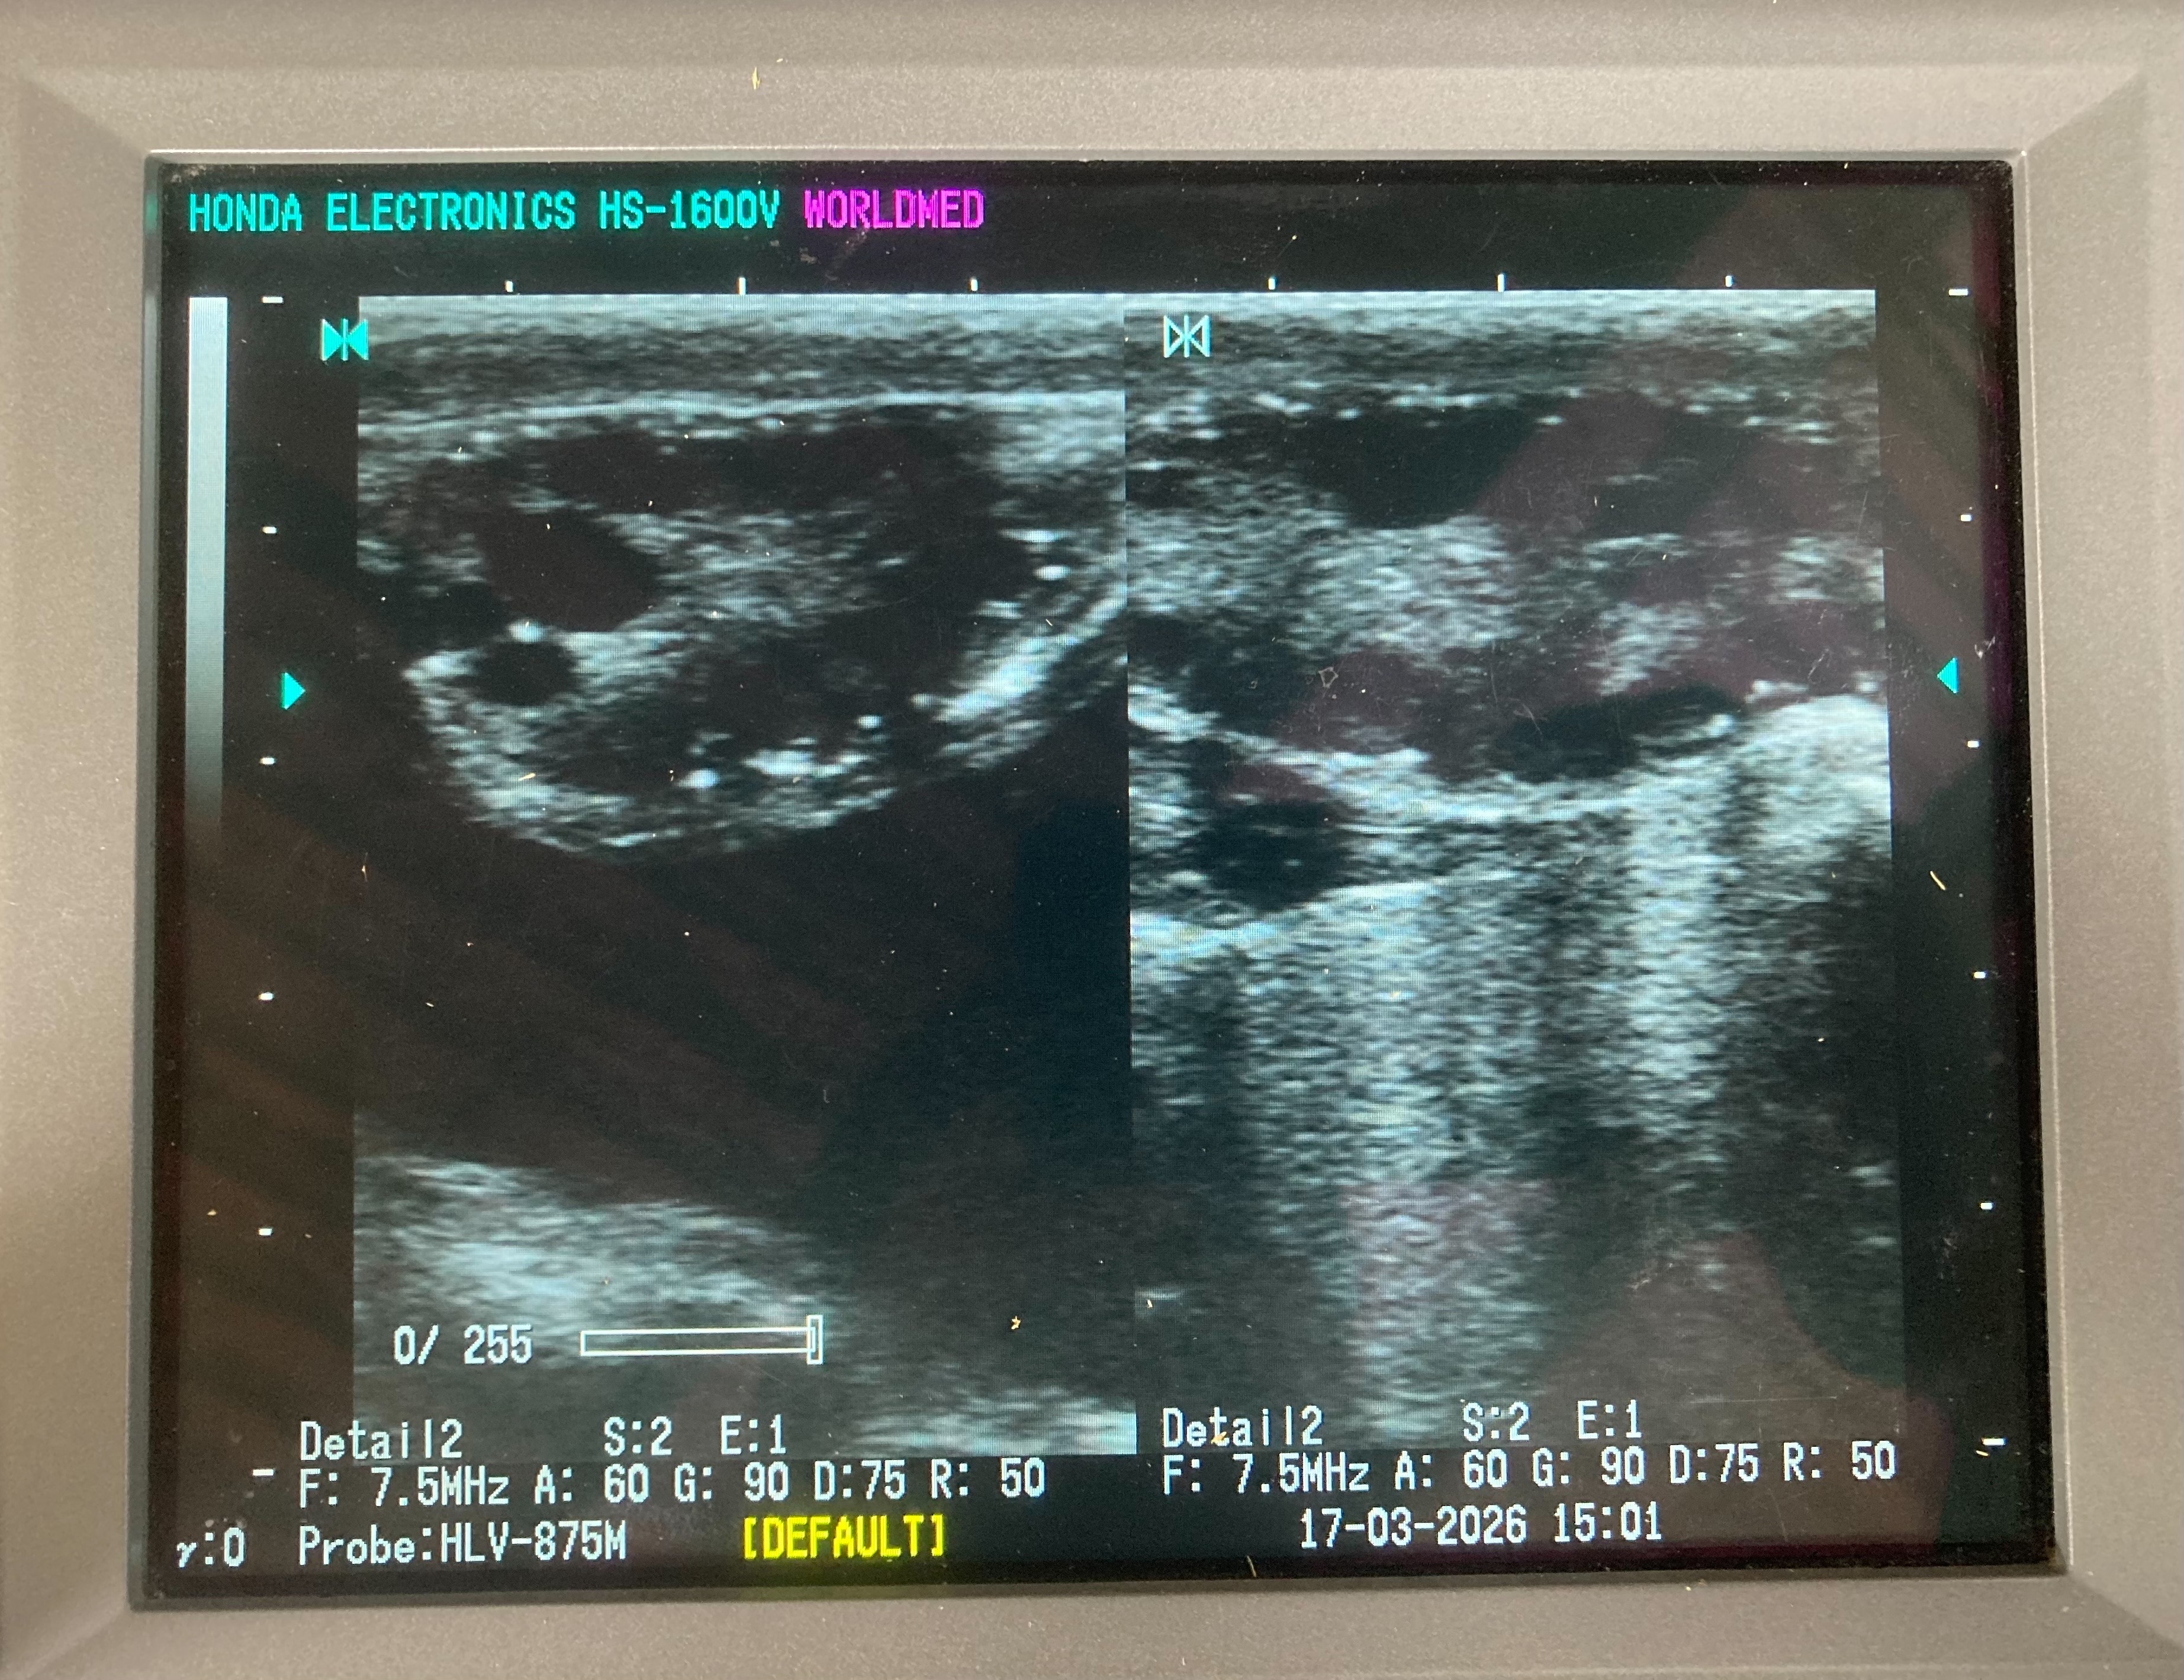

ตรวจท้องโคนม จำนวน 3 ตัว (พบโคท้อง 1 ตัว)

ตรวจระบบสืบพันธุ์ พร้อมแก้ไขปัญหา จำนวน 2 ตัว